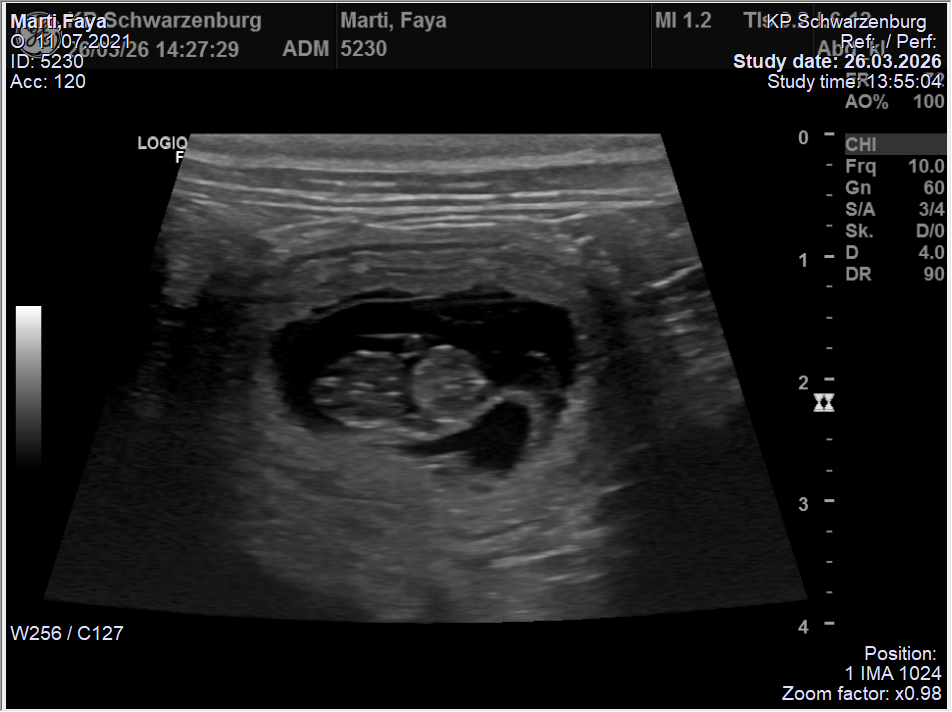

Nun heisst es weiter „brüten“ bis die Welpen Ende April auf die Welt kommen…